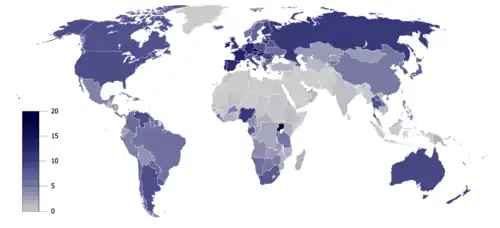

Europa

Aproximadamente el 10 % y el 3 % de los diagnósticos de cáncer en hombres y mujeres europeos, respectivamente, se atribuyen al consumo de alcohol.[14]

Europa: Un estudio de 2011 reveló que uno de cada 10 de todos los cánceres en hombres y uno de cada 33 en mujeres estaban causados por la ingesta pasada o actual de alcohol[15][16]

Australia

Australia: Un estudio de 2009 encontró que 2100 australianos mueren de cáncer relacionado con el alcohol cada año.[17]